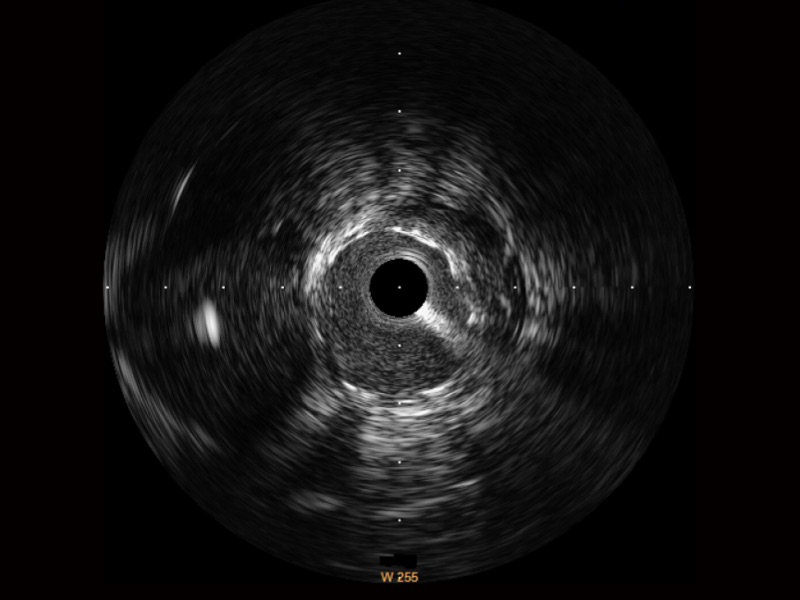

传统IVUS图像

对比传统IVUS导管成像,球速体育入口宽频IVUS图像的近场支架梁显影更细腻,远场中膜外血管仍清晰可辨,兼顾远中近,兼顾分辨力与穿透深度